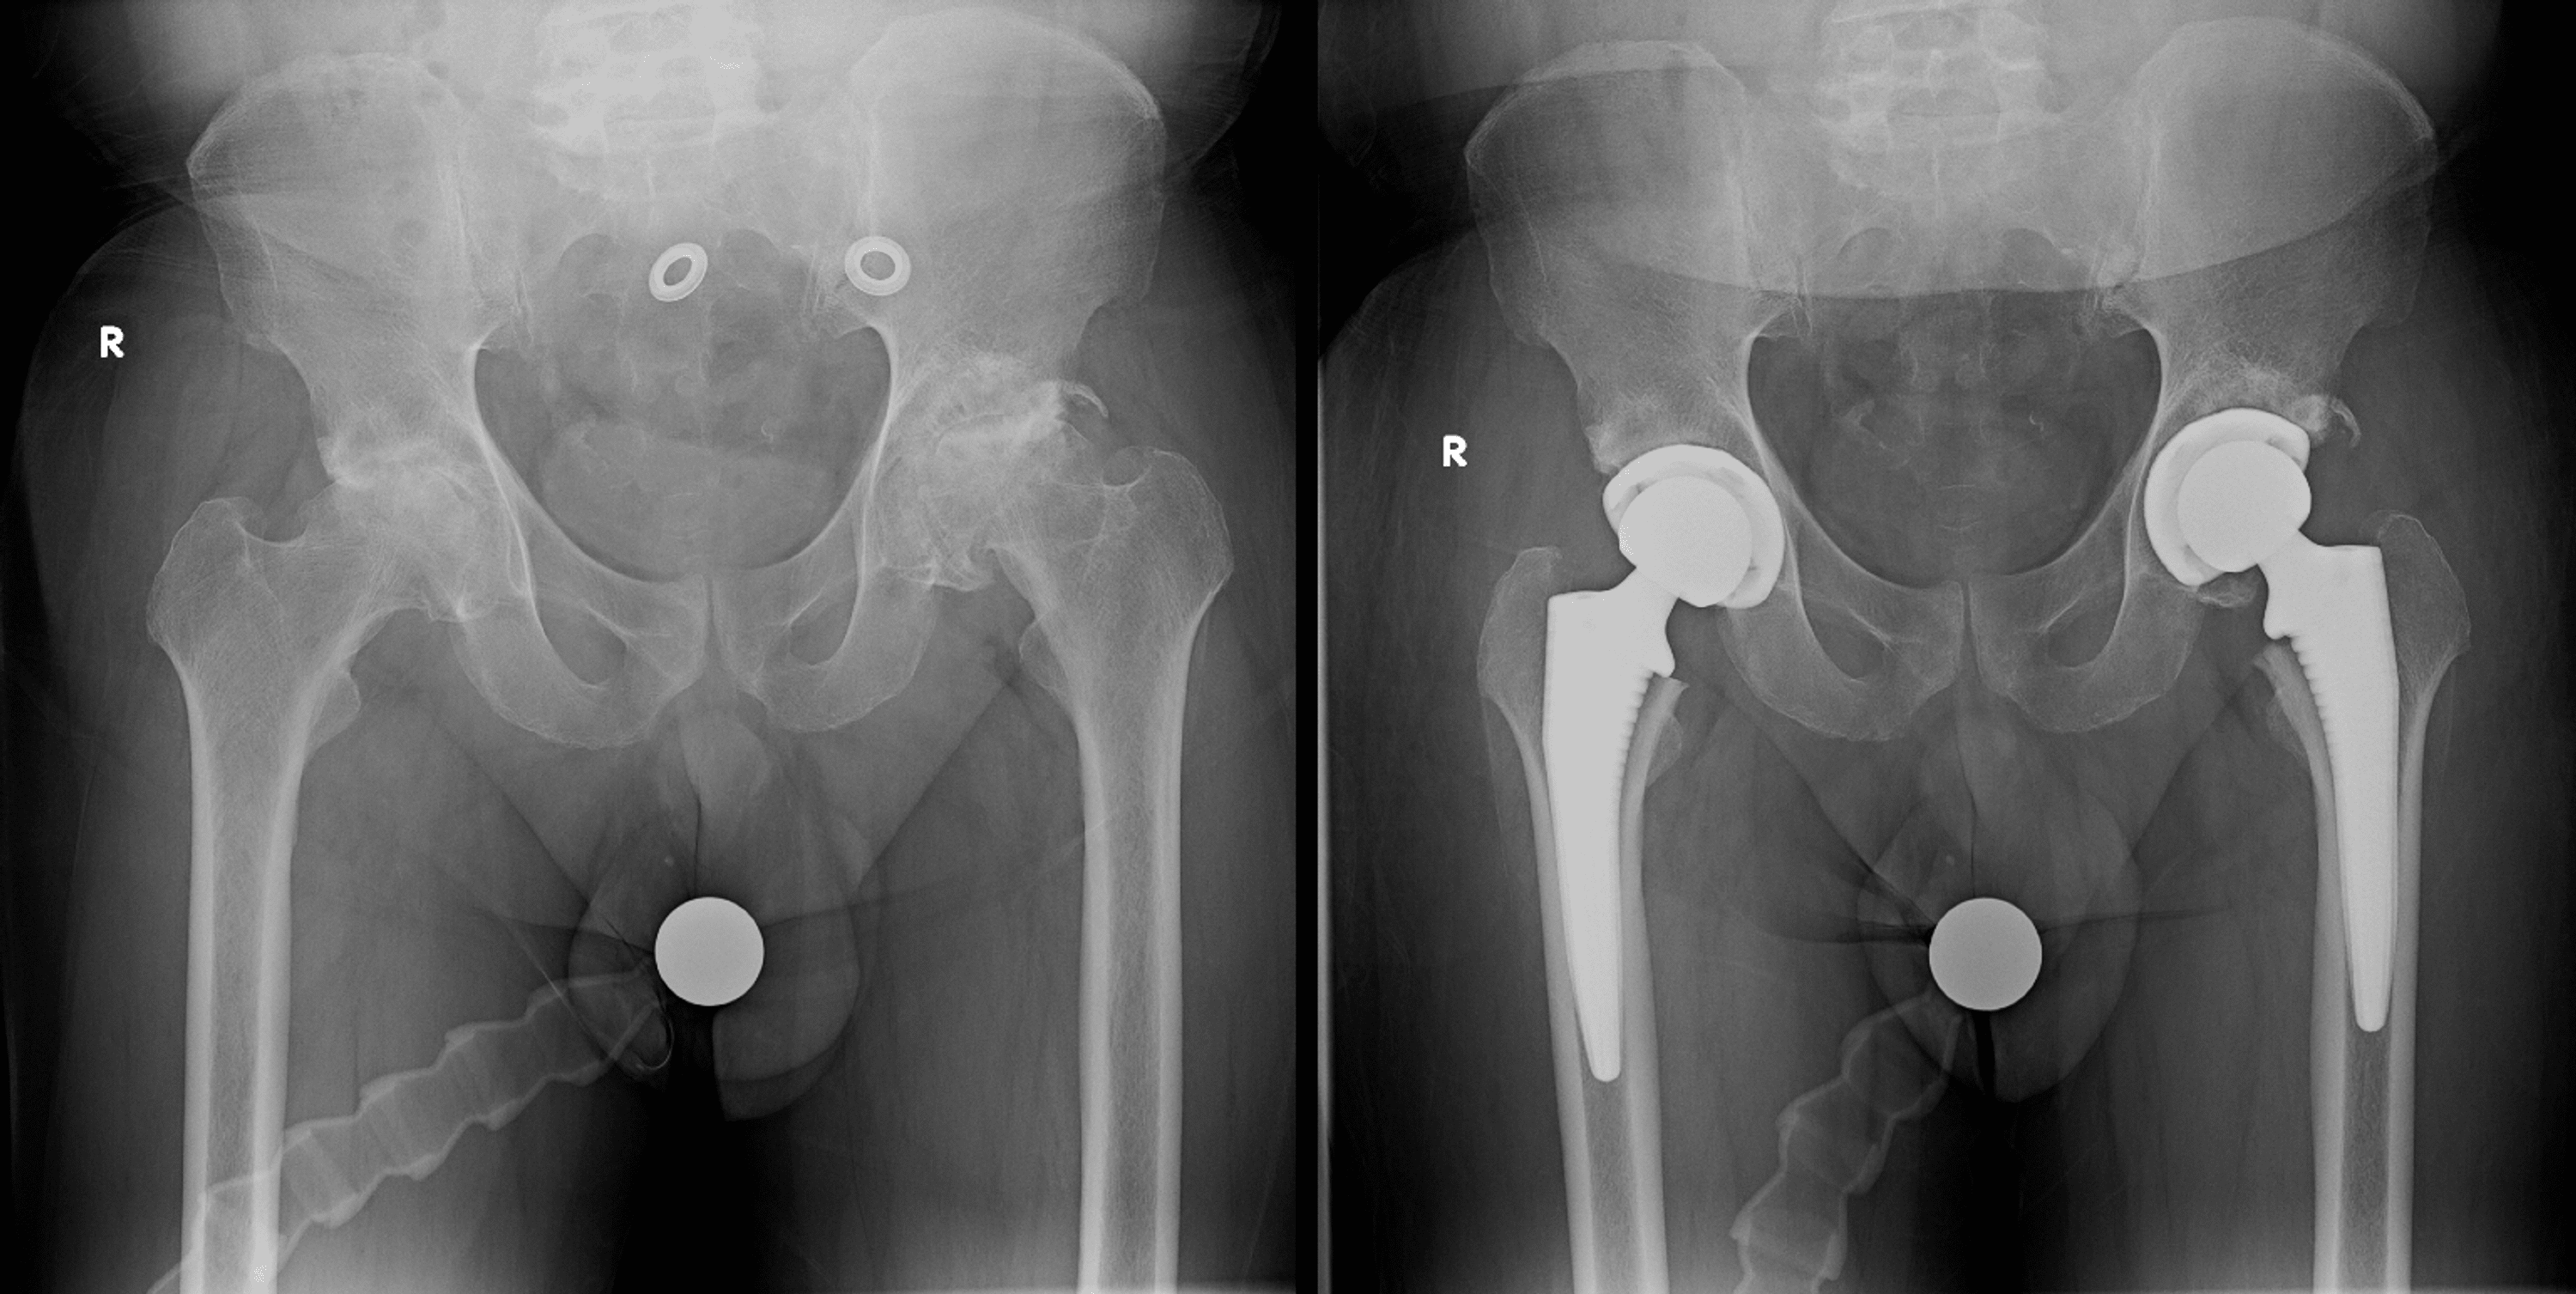

from radiopaedia.org

Dislocation of hip replacement Image

Dislocation of hip replacement Image Hip Replacement With Ms these results suggest that pain reduction is a realistic outcome of total knee or hip arthroplasty in people with ms and that. results of a recent study suggest that pain reduction is a realistic outcome of total knee or hip arthroplasty. due to gait disorders and a higher prevalence of osteoporosis, specific osteological evaluation and treatment should. Hip Replacement With Ms.